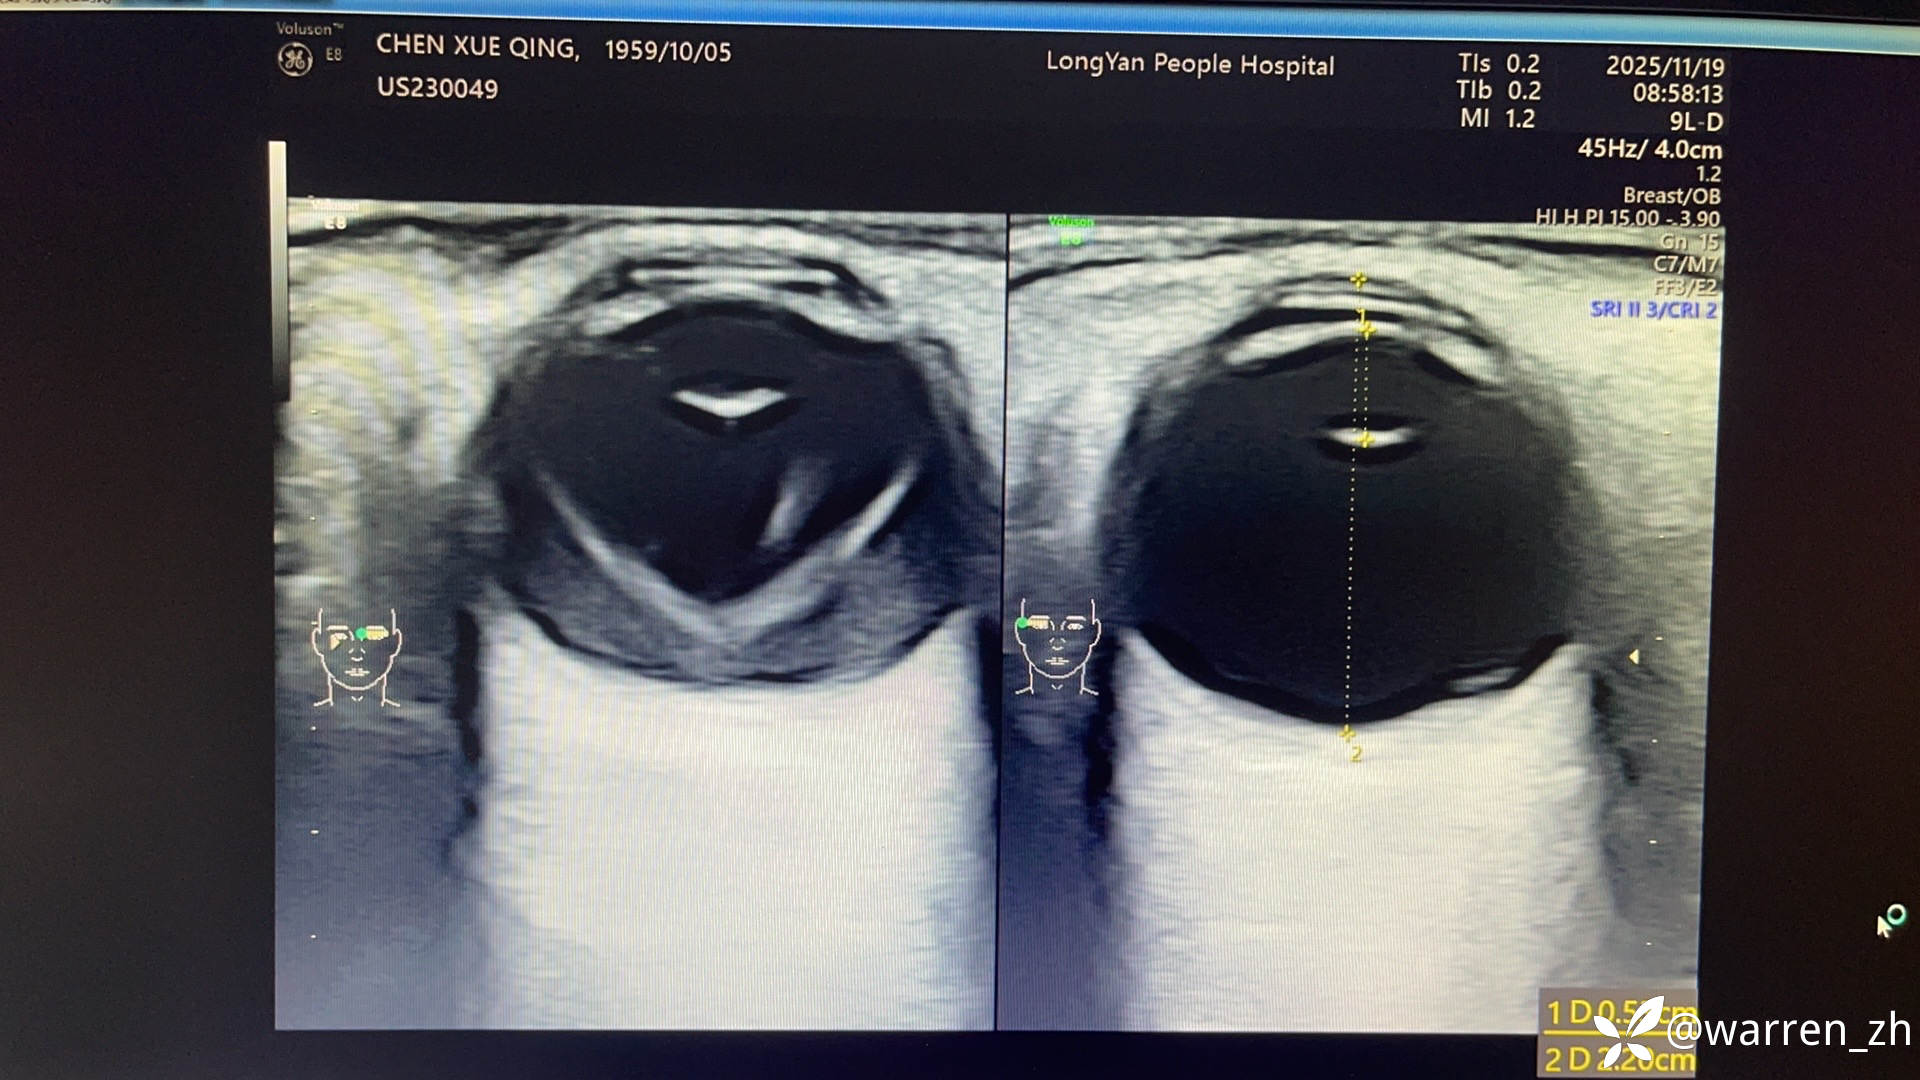

患者,男,65岁,左眼视力下降3个月,糖尿病史20年。检查,右眼视力0.1,左眼手动,光定位尚可,晶体轻度浑浊,眼底右眼网膜前出血,左眼玻璃体黄色浑浊,余窥不清,B超如图

考虑增殖性糖尿病视网膜病变玻璃体积血,视网膜脱离?增值膜?玻切手术要注意什么?